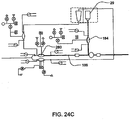

- Fig. 1 is a schematic representation of a hemodialysis system.

- the system 5 includes two flow paths, a blood flow path 10 and a dialysate flow path 20.

- Blood is drawn from a patient.

- a blood flow pump 13 causes the blood to flow around blood flow path 10, drawing the blood from the patient, causing the blood to pass through the dialyzer 14, and returning the blood to the patient.

- the blood may pass through other components, such as a filter and/or an air trap 19, before returning to the patient.

- anticoagulant may be supplied from an anticoagulant supply 11 via an anticoagulant valve 12.

- a dialysate pump 15 draws dialysate from a dialysate supply 16 and causes the dialysate to pass through the dialyzer 14, after which the dialysate can pass through a waste valve 18 and/or return to the dialysate feed via dialysate pump 15.

- a dialysate valve 17 controls the flow of dialysate from the dialysate supply 16.

- the dialyzer is a type of filter having a semi-permeable membrane, and is constructed such that the blood from the blood flow circuit flows through tiny tubes and the dialysate solution circulates around the outside of the tubes. Therapy is achieved by the passing of waste molecules (e.g., urea, creatinine, etc.) and water from the blood through the walls of the tubes and into the dialysate solution. At the end of treatment, the dialysate solution is discarded.